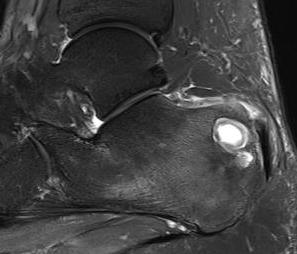

Talus

1. Head and neck

- medial approach between Tibialis anterior and Tibialis posterior

2. Body

- lateral Ollier's approach between Peroneus tertius and Peroneus brevis

Calcaneum

Direct lateral approach